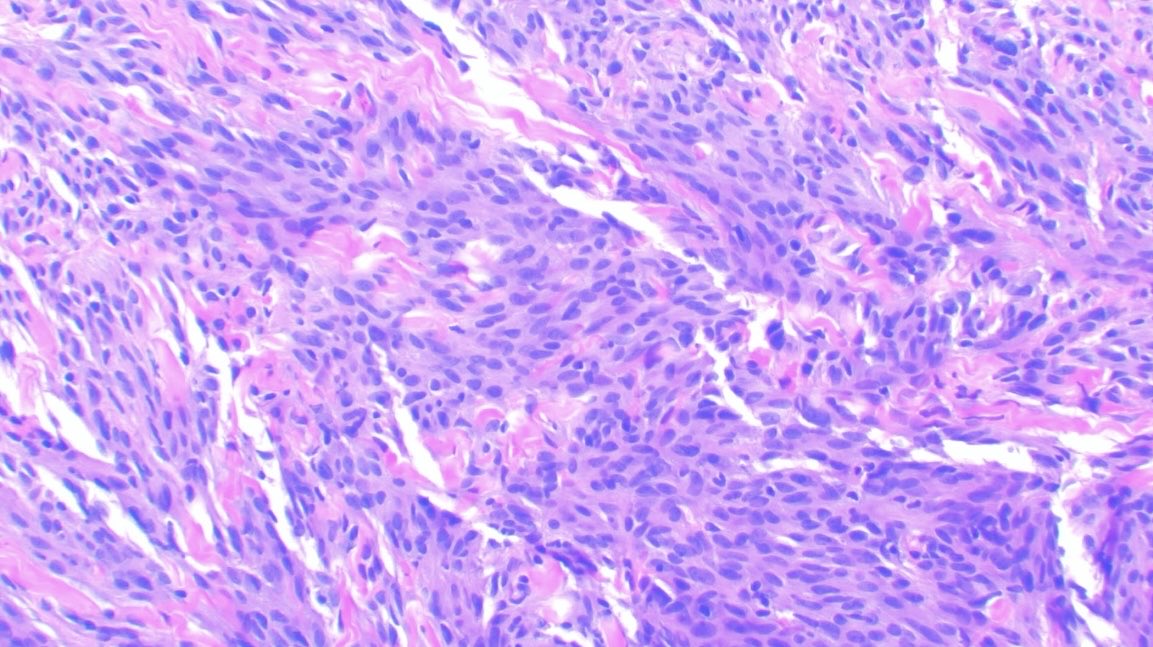

Dermatofibrosarcoma protuberans The presence of tumor cells between fat lobules results in a characteristic honeycomb appearance. #path #dermpath #pathology